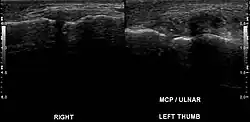

Stener lesion on left thumb in ultrasound

A Stener lesion is a type of traumatic injury to the thumb. It occurs when the aponeurosis of the adductor pollicis muscle becomes interposed between the ruptured ulnar collateral ligament (UCL) of the thumb and its site of insertion at the base of the proximal phalanx. No longer in contact with its insertion site, the UCL cannot spontaneously heal.[1]